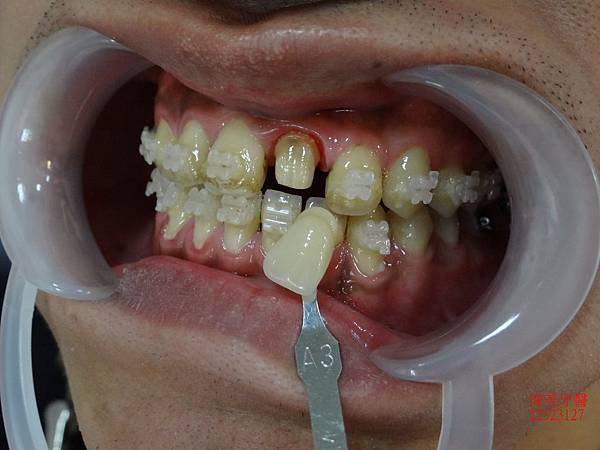

治療中~~~~

患者覺得非常開心,因為朋友在其他診所治療,都不敢相信他的療程進展如此神速~~~~~

上排牙齒已經恢復到正常咬合的位置點囉!!